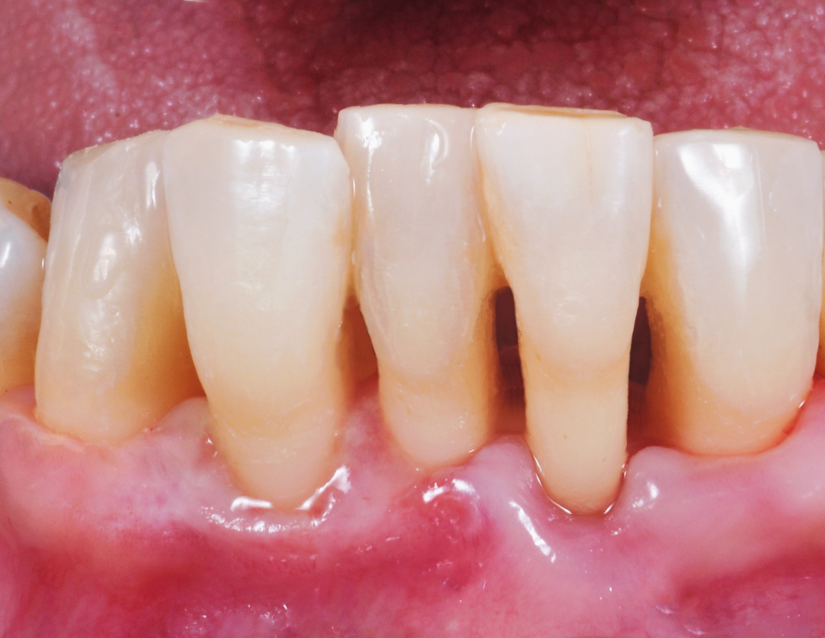

Gingivitis

inicios de gingivitis - Periodoncia - Clinica Dental Jardines

La gingivitis se caracteriza por la inflamación y el enrojecimiento de las encías, causados por la acumulación de placa bacteriana.